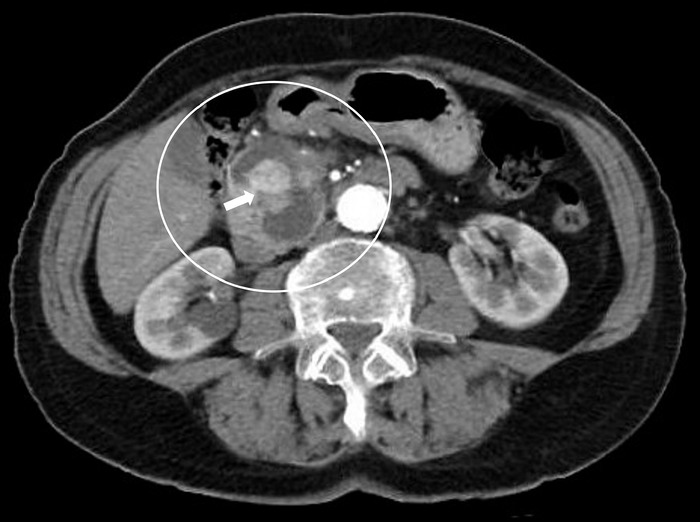

Case report: We report the case of a patient who developed a pancreatic metastasis from a classic variant papillary thyroid carcinoma 11 years after total thyroidectomy, cervical lymphadenectomy, and radioactive iodine ablation. The patient experienced increased thyroglobulin levels, and abdominal computed tomography scan revealed a lesion in the uncinate process of the pancreas. Tissue samples obtained by endoscopic ultrasound-guided biopsy were positive for thyroglobulin and thyroid transcription factor 1. Because the patient was not a candidate for surgery, the metastatic lesion was not iodine-avid, and tyrosine kinase inhibitors could not be offered because of tumor-related symptoms, the patient was treated with stereotactic body radiotherapy only. The patient died almost 2 years after the diagnosis of metastatic papillary thyroid carcinoma to the pancreas (13 years after total thyroidectomy for the primary cancer).